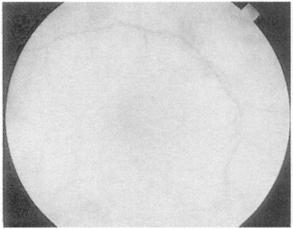

在熟悉之前你需要看一些视网膜图,花时间去注意黄斑,为一淡红色斑点。按顺序描述你的所见为佳,寻找背景,不是乳头或黄斑,而是出血和渗出,检查视网膜血管,注意粗细和规则——小动脉的直径是静脉的2/3,分布规则。正常的视乳头和糖尿病、高血压、乳头水肿和视神经萎缩见图(图151~155)。

图151 正常的视神经盘和视网膜

图152 糖尿病眼底的改变,可见斑点状出血和渗出

图153 高血压病眼底改变,可见血管屈曲

图154 视神乳头水肿,可见神经盘处模糊

图155 视乳头肥大,可见神经盘变清晰、苍白